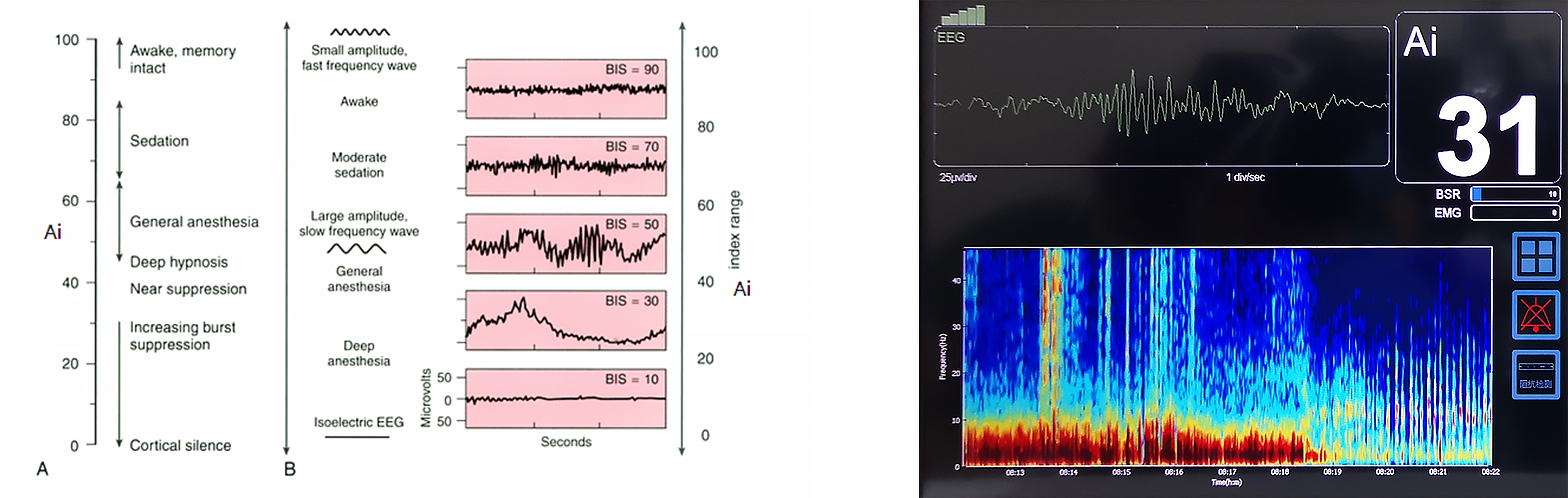

In clinical studies of EEG signaling, profound changes in EEG signals from waking to general anesthesia were accompanied by brain spontaneous electrical activity. The investigator propose to evalsuate the depth of anesthesia with the EEG signal. The important feature is the gradual deepening of anesthesia EEG signal as follows: 1. Disorganized high-frequency signal activity occurs; 2. The frequency and amplitude of EEG signals become more regular, especially in the δ-wave frequency band; 3. The frequency mixing of low-frequency band and high-frequency band occurs, and δ-wave activity occurs under deep anesthesia; 4. The anesthesia deepens, and the burst suppression signal appears. The deeper the anesthesia, the longer the suppression period will be; 5. Equipotential activity will occur at the end.

Basic principle of Ai anesthesia depth index: Ai anesthesia awareness index is based on multiple indicators such as frequency, double frequency, time domain and complexity.Multivariate statistical methods were used to quantify the brain waves from the awake to the deepest anesthetic state.